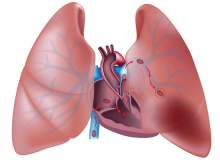

Akciğer Embolisi Nedir?

Çok basit bir tanımlamayla akciğer embolisi, akciğer atardamarının kan pıhtısıyla tıkanması sonucu ortaya çıkan klinik bir tablodur.